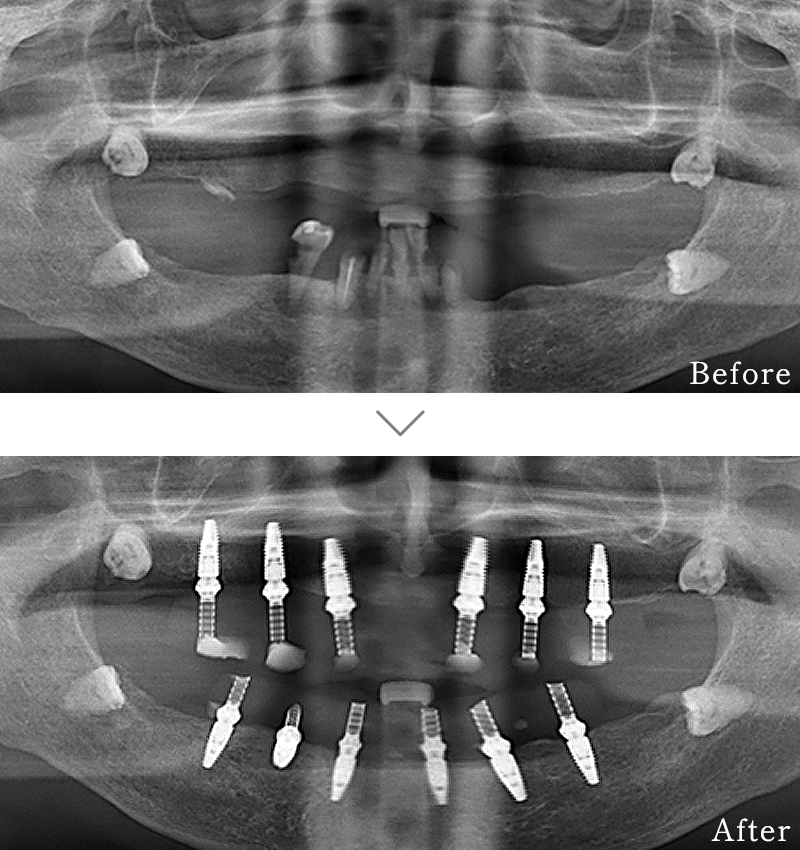

主訴 入れ歯も合わず、しっかりと噛んで食事ができないとのことで来院されました。

治療法 上下ともにALL-ON-6と呼ばれる最少本数のインプラントで全ての歯を回復する治療を行なっています。歯の部分は全てセラミックで作成されています。

治療期間 5ヶ月

費用 CT:16,500円(税込)

+ 静脈内鎮静法:77,000円(税込)

+ ALL-ON-6×2:5,500,000円(税込)

合計:5,593,500円(税込)